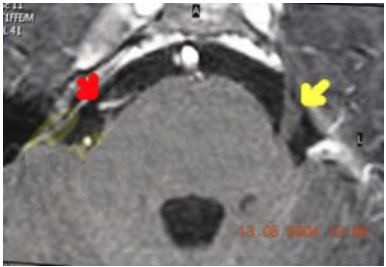

Il trigemino emerge dalla superficie laterale del ponte mediante una radice sensitiva più voluminosa e una radice motoria più piccola. La zona di passaggio tra mielina centrale e periferica, detta root entry zone, è particolarmente importante perché rappresenta il tratto più delicato nella fisiopatologia della nevralgia classica.

In molti casi il conflitto neurovascolare si localizza proprio in questa regione prossimale, dove il nervo è più vulnerabile a irritazione, demielinizzazione focale e scariche anomale.

Rapporti vascolari

Vicino alla radice del trigemino possono decorrere vasi arteriosi o venosi che, in alcune situazioni, entrano in contatto con il nervo. Questo aspetto è centrale nella comprensione della nevralgia trigeminale classica e nella logica della decompressione microvascolare.